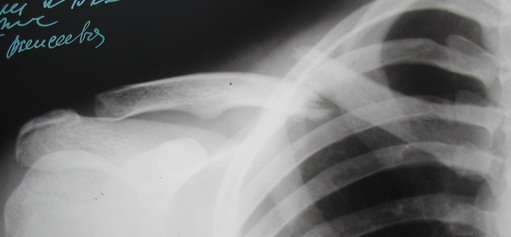

Во время стажировки в Австрии не мог не поинтересоавться, как австрийские хирурги лечат переломы ключицы. Оказалось, при переломах без смещения или с небольшим смещением накладывают восьмиобразную повязку, в остальных случаях выполняют остеосинтез пластинами.

Профессору Эмануэлю Трояну я рассказал про рамку Чижина и показал несколько фотографий своих больных с хорошими результатами после применения рамки. Профессор сказал, что прототипом рамки Чижина, наверняка, являлась повязка Белера. Уж очень они похожи. Затем